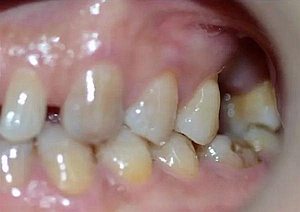

患者:男,37歲。左上后牙確實(shí)多年。既往體健,否認(rèn)麻醉和牙槽外科禁忌。

術(shù)前口內(nèi)照